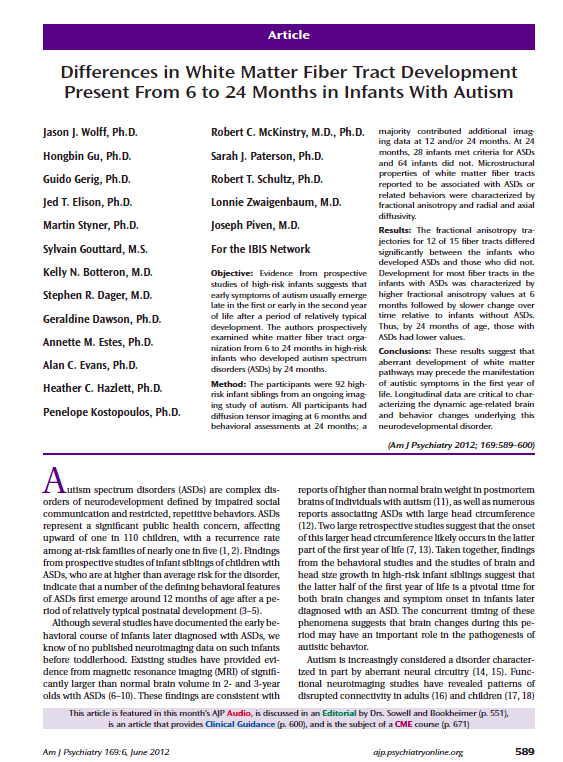

Imaging Data

1. Acquisition & Storage

2. Visualisation:

Imaging Browser, BrainBrowser3. Quality Control:

Radiological Review Module, DCC MRIData Querying

- Imaging Statistiscs

- Data Querying Tool (DQT)

What can LORIS do (pointform)

- Long Term Storage - Large datasets are valuable assets (e.g. ADNI)

- Anonymity/Privacy - Ethics/IRB compliance and patient confidentiality

- Data Sharing - Cross project collaborations

- Heterogeneous Data Management - Single platform for MRI, PET, Clinical & Genetics data

- Multimodal Data Querying - Easy querying of data, without requiring a programmer

- Quality Control - Protocol violations, artefact detector, inter-rater reliability

- Visualization - 3D and 4D

Imaging Browser

Imaging Quality Control

Testimonials

"You don't understand... LORIS saved our lives ... We could share our data anywhere. LORIS makes it really hard to share incorrect data. The quality control data is right there. You can share the QC... it's so well QCed" -- Angelina Paolozza (NeuroDevenet, 2015)